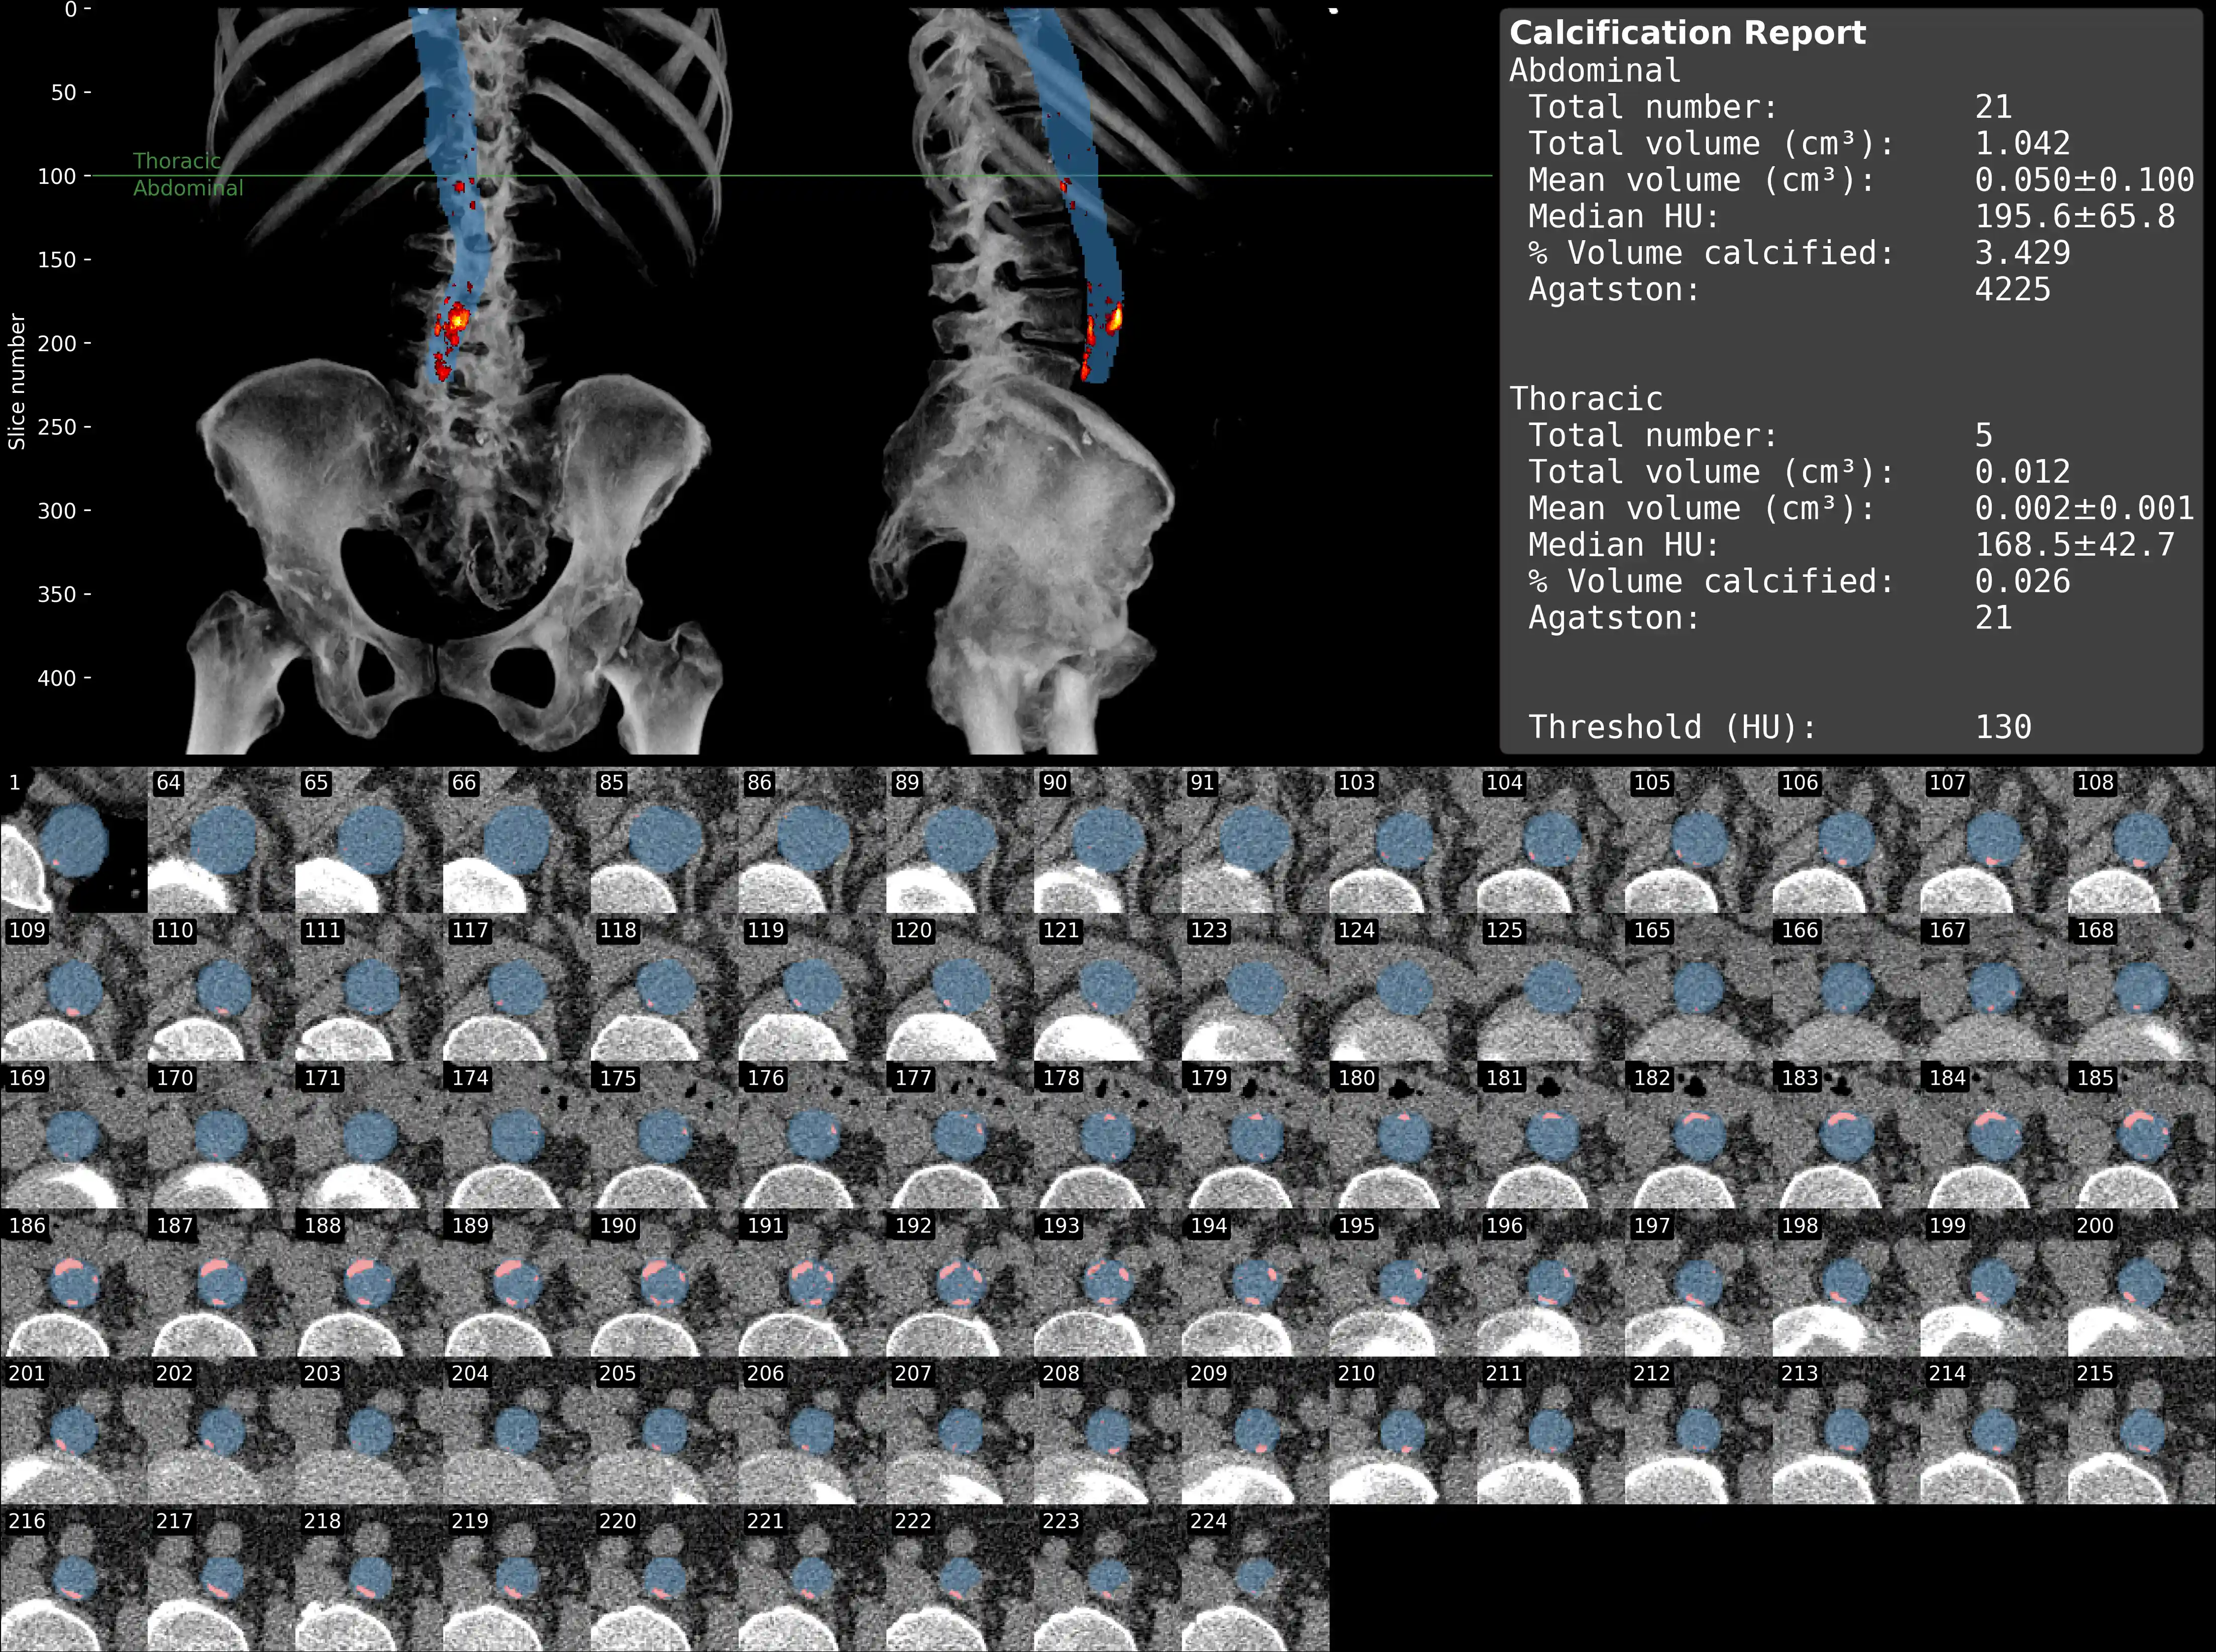

Abdominal Aortic Calcification Segmentation

- The visualization presents coronal and sagittal MIP projections with the aorta overlay, featuring a heat map of calcifications alongside extracted calcification metrics. Below is a mosaic of each aortic slice with calcifications.

Example Output

Statistics on aortic calcifications:

Abdominal:

Total number: 21

Total volume (cm³): 1.042

Median HU: 195.6+/-65.8

Mean volume (cm³): 0.050+/-0.100

Threshold (HU): 130.000

% Calcified aorta 3.429

Agatston score: 4224.7

Thoracic:

Total number: 5

Total volume (cm³): 0.012

Median HU: 168.5+/-42.7

Mean volume (cm³): 0.002+/-0.001

% Calcified aorta 0.026

Agatston score: 21.1